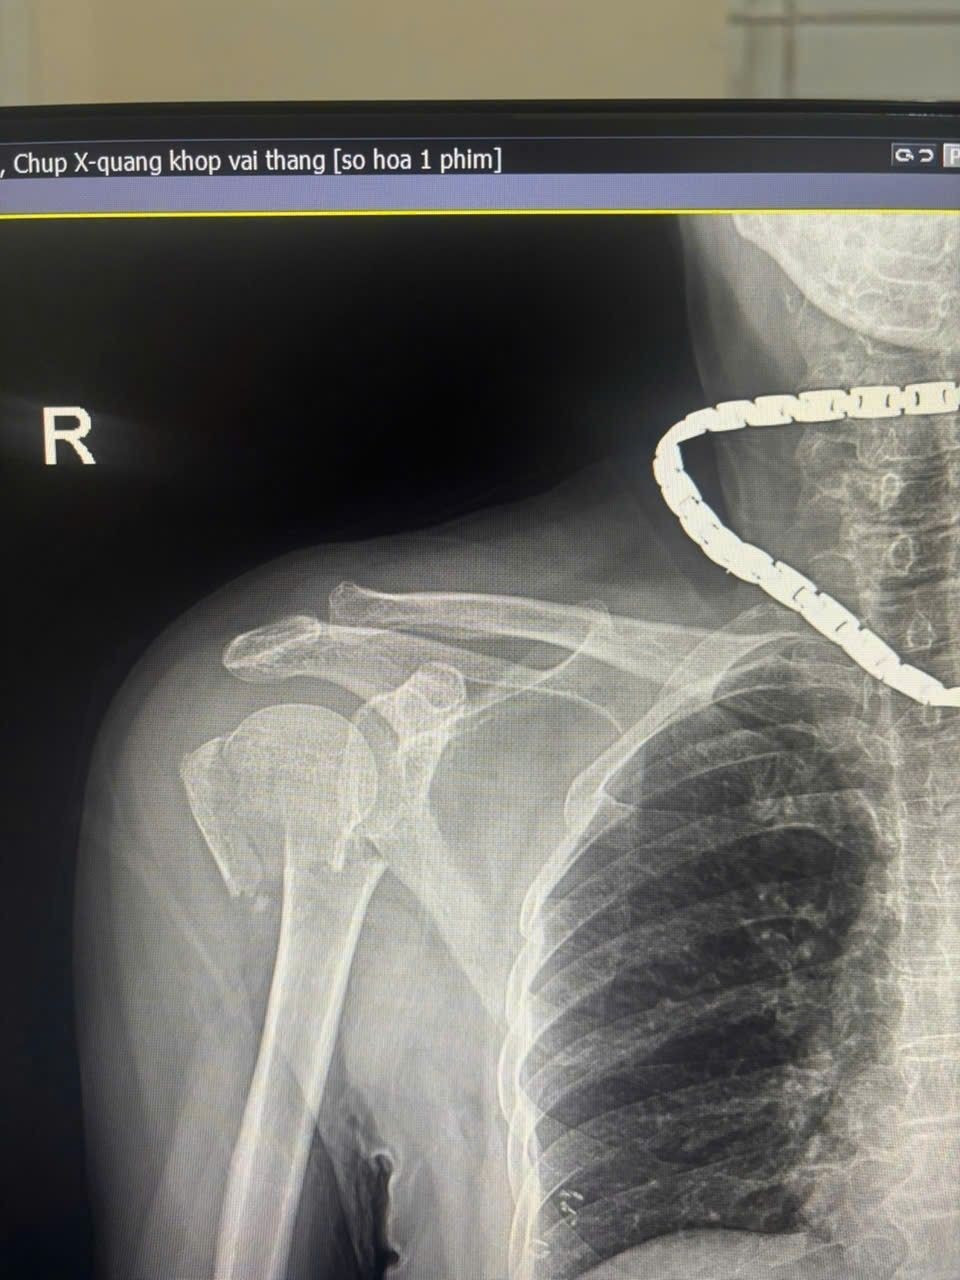

xuong-canh-tay-1.jpg

Ngay sau phẫu thuật, bệnh nhân phục hồi tiến triển tốt, giảm đau rõ rệt, vận động khớp vai cải thiện từng ngày và tinh thần ổn định.